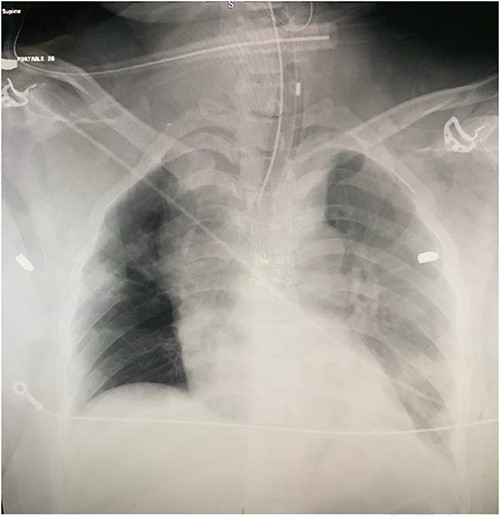

A 37-year-old female was brought to the trauma unit after sustaining multiple gunshots to the chest and abdomen. She was alert, conscious, and hemodynamically stable. The first responders mentioned that the patient was complaining of severe right lower limb pain at the scene. Physical examination revealed a gunshot wound in the suprasternal area with hematoma. Therefore, the patient was intubated to protect her airway. Several gunshot wounds were identified over the anterior aspect of her body, including bilateral sides of her head, central neck zone 1, right second intercostal space at mid clavicular line, and right upper quadrant of her abdomen. On the posterior aspect, two wounds over the right paraspinal area and another over the subcapsular area. She had diminished distal pulses in the right lower limb. Her chest x-ray revealed three bullet fragments: one adjacent to the right acromioclavicular junction in the right scapula and another projecting over the left scapula. Bilateral chest tubes were inserted. Extended focused assessment sonography for trauma was negative (Fig. 1).

Chest CT showed three bullet fragments. One was adjacent to the right acromioclavicular junction, another was posterolateral to the right periscapular muscles, and the third was anterior to the left scapula (Fig. 4). In addition to right lung contusions, left fifth rib fracture with pneumothorax, and bilateral pleural hemothorax more at the left side.